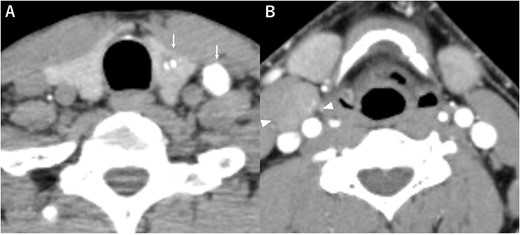

A 48-year-old man with a medical history of diabetes and pyorrhea alveolaris underwent computed tomography (CT). After the CT revealed a calcified mass in the left lobe of the thyroid and lymph nodes in the left cervical region, he was referred to our hospital. A solid mass was palpated in the left lobe of the thyroid and the left cervical lymph nodes. However, a soft mass was palpated in the right cervical region. He presented with no weight loss, no persistent fever and no night sweats (no B symptoms). Blood examination revealed that the patient was euthyroid, with a normal thyroglobulin level (17.4 ng/ml), a negative thyroglobulin antibody and a slightly high level of soluble interleukin-2 receptor (360 U/ml). Ultrasonography revealed a hypoechoic mass (18 × 14 mm) with microcalcification in the left lobe of the thyroid and a similar mass in the left cervical lymph node (#VI, 18 × 11 mm). The right cervical lymph node was enlarged (#Vb, 24 × 12 mm), although it was hypoechoic internally and had no microcalcification, differentiating it from the primary lesion (Fig. 1). CT revealed calcified nodules in the left lobe of the thyroid and the left cervical lymph nodes, but the right cervical lymph node mass was not calcified and showed no contrast effect (Fig. 2). Fine needle aspiration was conducted, and the mass in the left lobe of the thyroid was cytologically diagnosed as PTC. However, the right cervical lymph node mass remained class II. Thus, we preoperatively diagnosed PTC, cT1b N1b M0 cStage I and speculated that the right cervical lymph node mass expanded due to an unknown inflammation or malignant lymphoma. Total thyroidectomy, left modified neck dissection and biopsy of the right cervical lymph node were performed. The pathological diagnosis was PTC, 13 mm, T1b N1b (Fig. 3), with the right cervical lymph node diagnosed as NLPHL. Histologically, large tumor cells LP cells, termed “popcorn cells” were observed against a background of nodular or nodular diffuse proliferation of small lymphocytes. Immunostaining revealed that LP cells were CD3 (–), CD5 (–), CD10 (–), CD15 (–), CD20 (+), CD30 (–), CD79a (+), BCL6 (+) and EBER (–) in a background of B-cell-rich lymphoid follicles (Fig. 4). A postoperative fluorodeoxyglucose (FDG)-positron emission tomography (PET)/CT revealed no other accumulation except for the right cervical lymph node. The patient was diagnosed with Stage IA NLPHL, according to the Ann Arbor classification. Postoperatively, NLPHL treatment was prioritized, and external radiation (30.6 Gy) was applied to the right neck. PTC was considered a high-risk category for recurrence due to extranodal invasion of lymph node metastasis, and radioactive iodine therapy (ablative dose, 1110 MBq) was administered. Both PTC and NLPHL showed no recurrence 18 months after surgery.

Computed tomography (A) calcified nodules in the left lobe of the thyroid and the left cervical lymph nodes (arrow), (B) the right cervical lymph node mass with no calcification or no contrast effect (arrowhead).